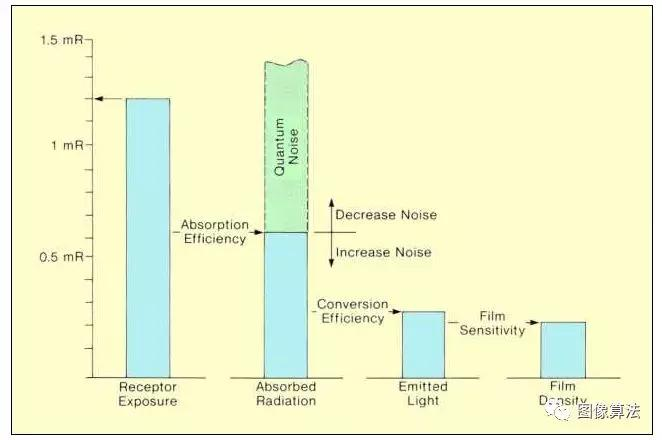

射线照相接收器(盒式磁带)的灵敏度取决于屏幕和胶片的特性以及它们的匹配方式。影响受体灵敏度的因素不一定会改变受体的量子噪声特性。影响射线照相受体灵敏度的主要因素是薄膜敏感性,屏幕转换效率和屏幕吸收效率。量子噪声水平由受体实际吸收的光子浓度决定 ,而不是传递给它的光子浓度。通过改变减少实际吸收的光子数量的任何因子来增加受体灵敏度 将增加量子噪声。

形成图像所需的受体暴露(受体敏感性)可以通过修改几个因素来改变,如下图所示。图中右侧所示的薄膜灵敏度决定了产生所需薄膜密度所需的光量。如果增加胶片的灵敏度以减少所需的光量,反过来,这将减少必须在屏幕中吸收的X射线光子的数量。结果将是具有增加的量子噪声的图像。回想一下,特定胶片和屏幕组合的有效灵敏度取决于胶片的光谱灵敏度特性与屏幕产生的光的光谱特性的匹配。当两个特征紧密匹配时,产生最大灵敏度和最大量子噪声。在射线照相术中,改变胶片的灵敏度(即改变胶片的类型)是调节图像中量子噪声水平的最直接方法。量子噪声通常是限制在射线照相中使用高灵敏度薄膜的因素。

强化屏 - 膜受体内辐射量的关系

转换效率是增强屏幕的特征,实际上是实际转换成光的吸收的X射线能量的分数。特定屏幕的转换效率值由其组成和设计决定。它不能被用户更改。原则上,高转换效率可提高受体灵敏度并减少患者暴露。不幸的是,转换效率的提高降低了必须在屏幕中吸收的x辐射量,这反过来又增加了量子噪声。因此,高转换效率并不总是增强屏幕的理想特性。制造商应将其调整到能够在受体灵敏度和量子噪声之间产生适当平衡的值。

在不增加量子噪声的情况下增加射线照相受体灵敏度的唯一方法是 提高吸收效率。吸收效率的提高不会改变产生图像所必须吸收的辐射量。然而,它确实减少了所需的入射暴露,因为更大比例的辐射被吸收。

回想一下,有几个因素决定了吸收效率:即屏幕组成,屏幕厚度和光子能谱。射线照相受体灵敏度和量子噪声之间的关系可总结如下。适当曝光图像中的量子噪声量与增强屏幕中实际吸收的X射线能量的量直接相关。影响吸收效率的变化因素,例如屏幕材料的类型,屏幕厚度和KVp(光子能量谱)将改变与量子噪声水平相关的整体受体灵敏度。另一方面,改变薄膜灵敏度,光谱匹配和增感屏的转换效率通常会改变量子噪声和受体灵敏度。